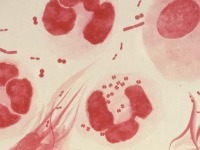

Expertos hallan primera cepa de gonorrea calificada de ´superbacteria´

Científicos hallaron en Japón una cepa de una ¨superbacteria¨ de la gonorrea que es resistente a todos los antibióticos recomendados y que podría transformar la infección que suele ser fácilmente tratable en una...